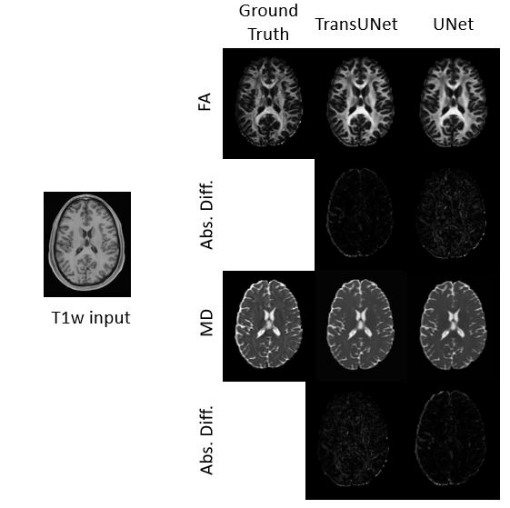

4.1.3 Visual Evaluation

When comparing the predicted FA and MD maps with the ground-truth DTI images, I noticed that the major white-matter pathways were still clearly recognizable in the predictions. Some of the finer details appeared a bit smoother, but the overall spatial patterns remained very close to the true images. This visual similarity aligns well with the quantitative evaluation.

Refer to caption

Figure 4: Prediction Results of FA and MD for TransUNet and UNet

Visually, the TransUNet synthesis is superior for both FA and MD compared to a UNet synthesis as both categories of parametric maps show less absolute difference leading to closer resemblance to the ground truth. The FA prediction by the TransUNet shows more precise boundaries between gray and white matter compared to the UNet and the MD prediction by the TransUNet shows more detailed information towards the borders of the parametric map.